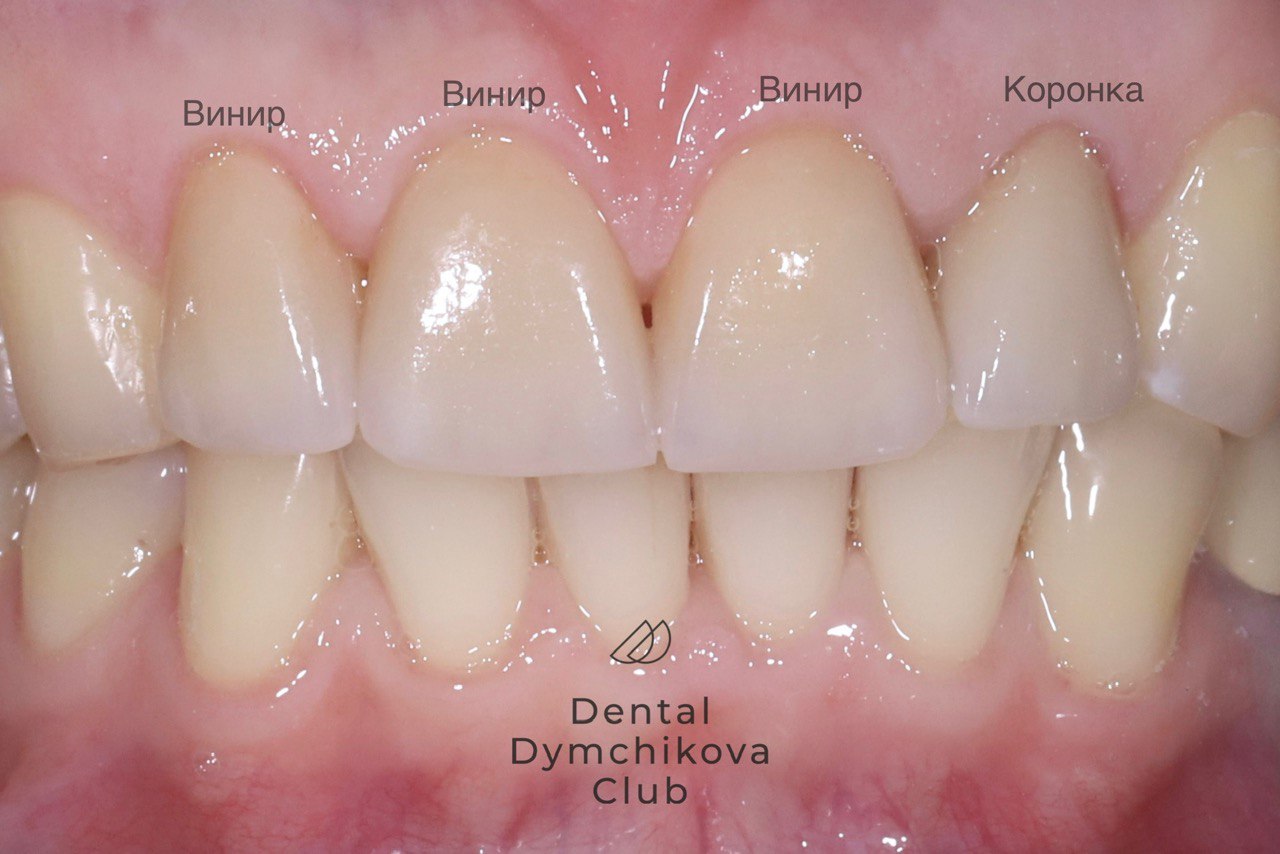

Виниры и коронка

Пациентка, 32 года

Жалобы: на старые пломбы на передних зубах.

Объективно: несостоятельные композитные пломбы, депульпированный зуб 1.1, живые зубы 1.2, 2.1, 2.2, 2.3, наблюдается кариес на живых зубах.

Лечение: установка коронки на зуб 1.1 и лечение кариеса и установка виниров Emax на зубы 1.2, 2.1, 2.2, 2.3.

Срок лечения: 2 недели (2 посещения).

Доктор: Дымчикова Анна Вавиловна